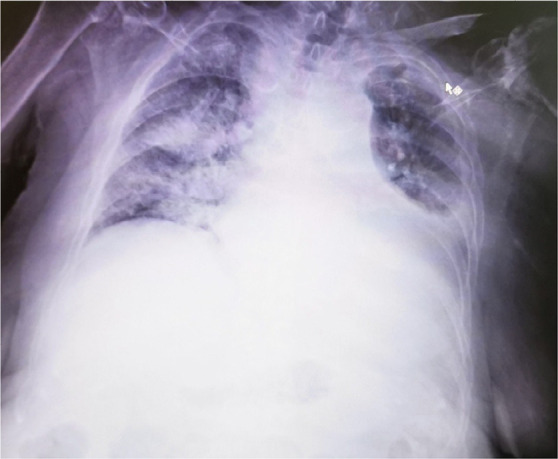

Case presentation: We present a case of a 77-year-old woman, who experienced a major flare, involving renal impairment, cardiorespiratory deterioration and pleuritis, along with signs of haemolytic anaemia, three weeks after a severe CDI. She received corticosteroids, rituximab (RTX), and cyclophosphamide (CYC), but the outcome was still fatal.